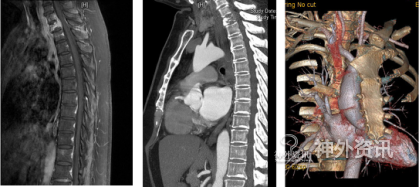

来自山东罹患乳腺癌的于女士,在乳腺癌根治术后14个月后出现胸背部疼痛,左上肢麻木等症状,胸椎MRI检查发现胸椎多个椎体信号异常,考虑乳腺癌转移,T1椎体病理性骨折。经过多方咨询,于女士在丈夫的陪同下,慕名来到北京清华长庚医院神经外科主任王贵怀教授的门诊就诊,希望能够得到彻底、安全的切除和治疗。

图1. 患者部分术前影像资料